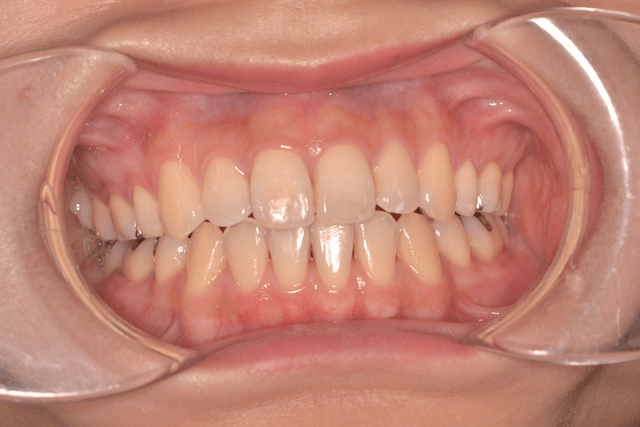

開咬(オープンバイト)を抜歯、インプラントアンカー、DBSで改善した症例

※DBSとはダイレクトボンディングシステムと呼ばれており、ブラケットにワイヤーを通して歯を動かしていく矯正治療です。

患者情報

16歳女性

主訴

前歯の隙間が気になる

行った治療内容

上顎両側4番抜歯、下顎左側1番抜歯 上顎インプラントアンカー、顎間ゴム、DBS

治療のリスク

歯根吸収、前歯部歯肉退縮

治療期間

3年6か月

※ クリックして拡大することができます。